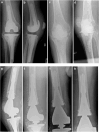

Distal Femoral Replacement With a Metaphyseal Sleeve: Outcomes and Risk Factors for Subsidence

In this study, we report on the outcomes of our experience using a metaphyseal sleeve with a distal femoral replacement (DFR) and review the risk factors for sleeve subsidence over a 3 year period.